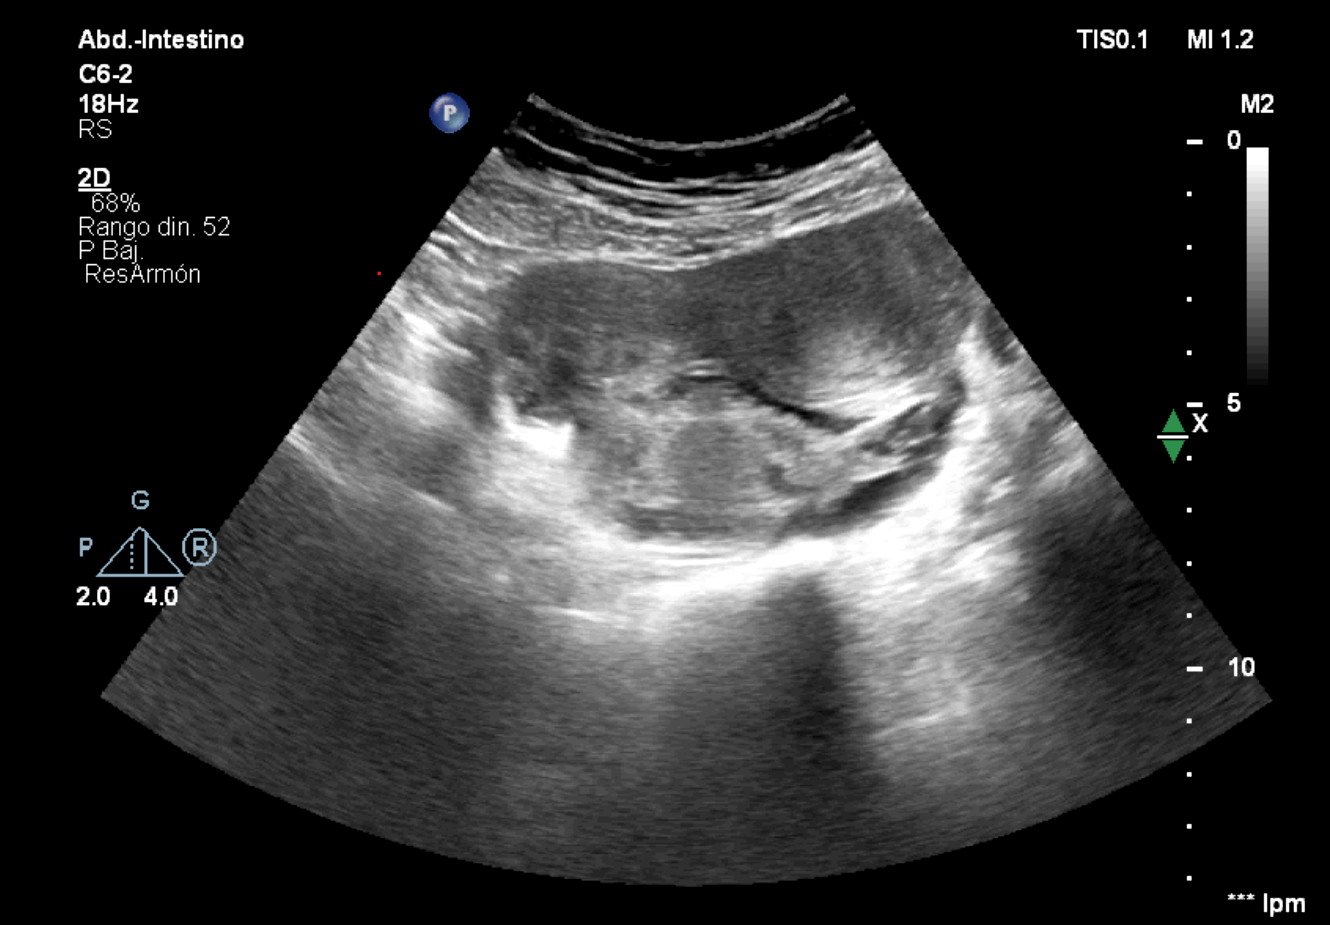

Ante la persistencia de dolor con pruebas anodinas, se realiza ecografía clínica.

Hallazgos ecográficos

En pelvis menor una estructura paranexial derecha de 76 x 36 mm, bien delimitada, y estructura tubular anecoica adyacente que parece corresponder a la trompa de Falopio dilatada.

Se contacta con Ginecología, repiten test de embarazo, positivo débil. Realizan nueva ecografía, corroborando hallazgos previos, compatibles con embarazo ectópico y hematosalpinx.